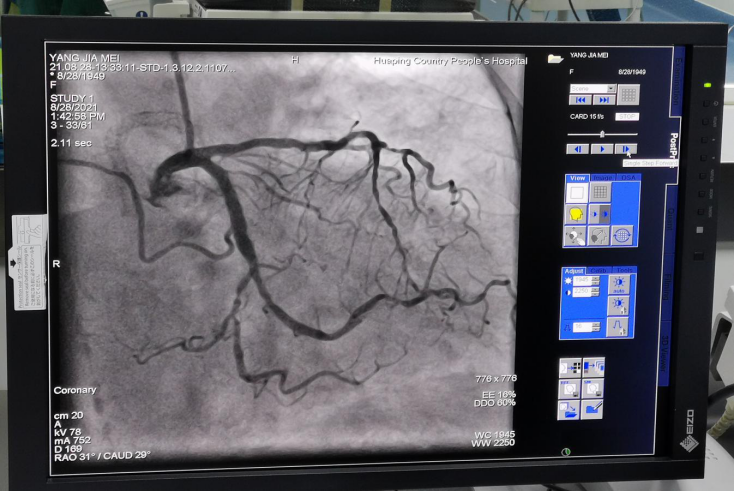

冠脉造影像一幅漂亮的“画”

在专家指导下,从8月27日到29日成功完成了20例心脏冠状动脉造影检查、5例心脏冠脉支架植入、3例颅脑动脉造影检查、2例心脏冠状动脉药物球囊植入、1例永久性心脏电生理起搏器植入,其中做了1例急诊冠状动脉造影+支架植入。所有患者在术中术后安全、平稳、顺利,痛苦较小,术后各种不适症状明显减轻。此次介入检查治疗的各项工作受到患者及家属的良好评价。